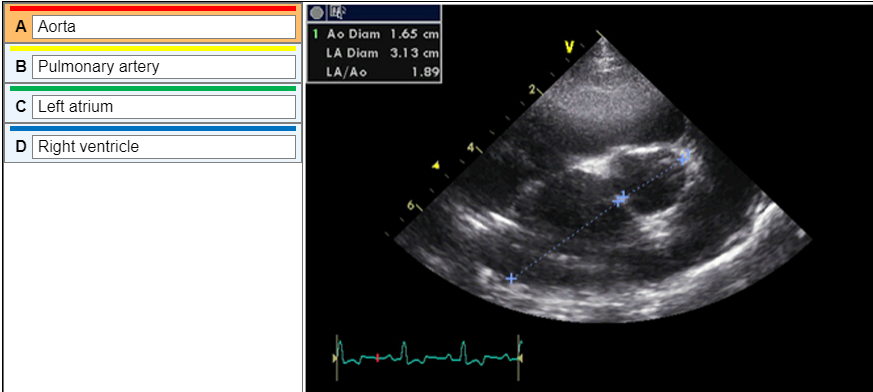

• label the image

A) D

B) C

C) A

D) B